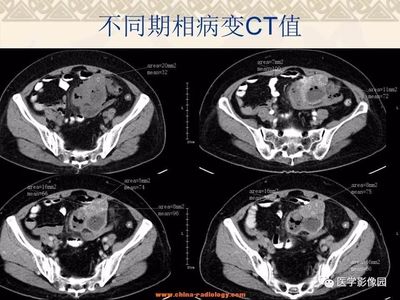

不是,只是怀疑,需要进一步诊断。那还是太片面了。一般还有其他指标可以参考。内镜(EUS)能清晰显示胃壁的五层结构,准确探查肿瘤的起源水平、体积、边界及回声模式。是目前诊断黏膜下肿瘤最准确的方法,也是术前诊断和评估间质瘤最有价值的手段。EUS超声显示:胃壁固有肌层低回声病变,回声略高于正常固有肌层;